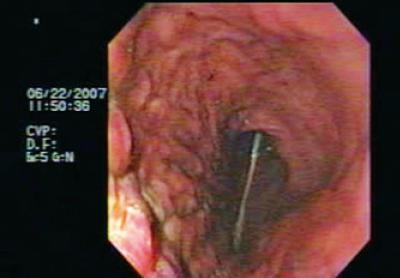

Patient was referred for endoscopy which found an organoaxial gastric volvulus (Figure 8) and a para-esophageal hiatal hernia. Endoscopic devolvulation was decided upon. An alpha shaped loop was initially placed (Figure 9), followed by passage of the endoscope to the antrum. Clockwise rotation of the equipment and consequent devolvulation were then performed (Figure 10). The patient was referred to the outpatient clinic for treatment of his para-esophageal hernia.

Figure 10. Observe how the gastric cavity has recovered its usual distribution. The folds of the greater curvature are at the lower part of the screen, and there is easy access to the antrum.